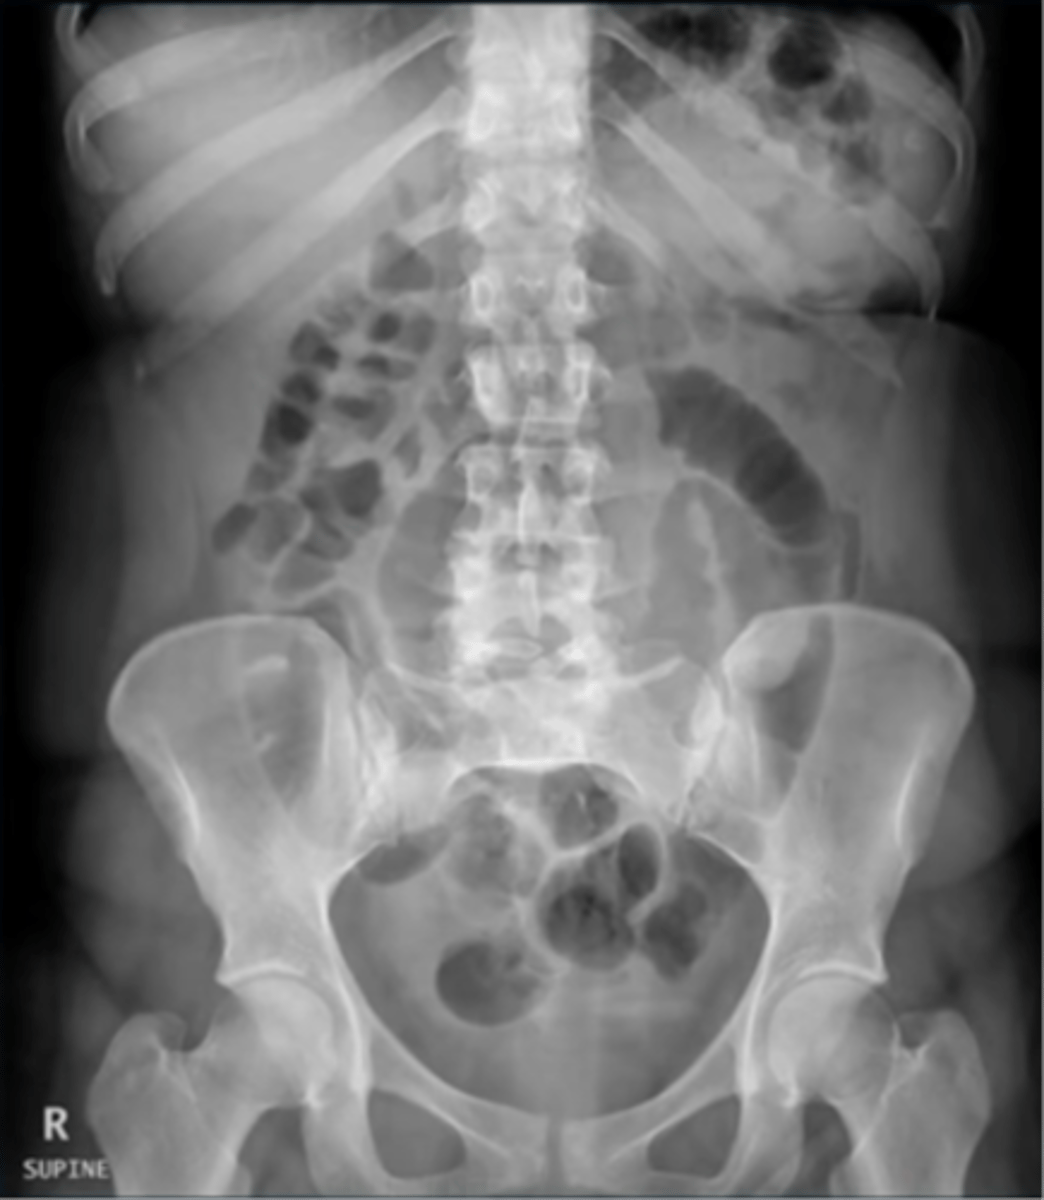

Normal bowel gas pattern

Normal supine AXR